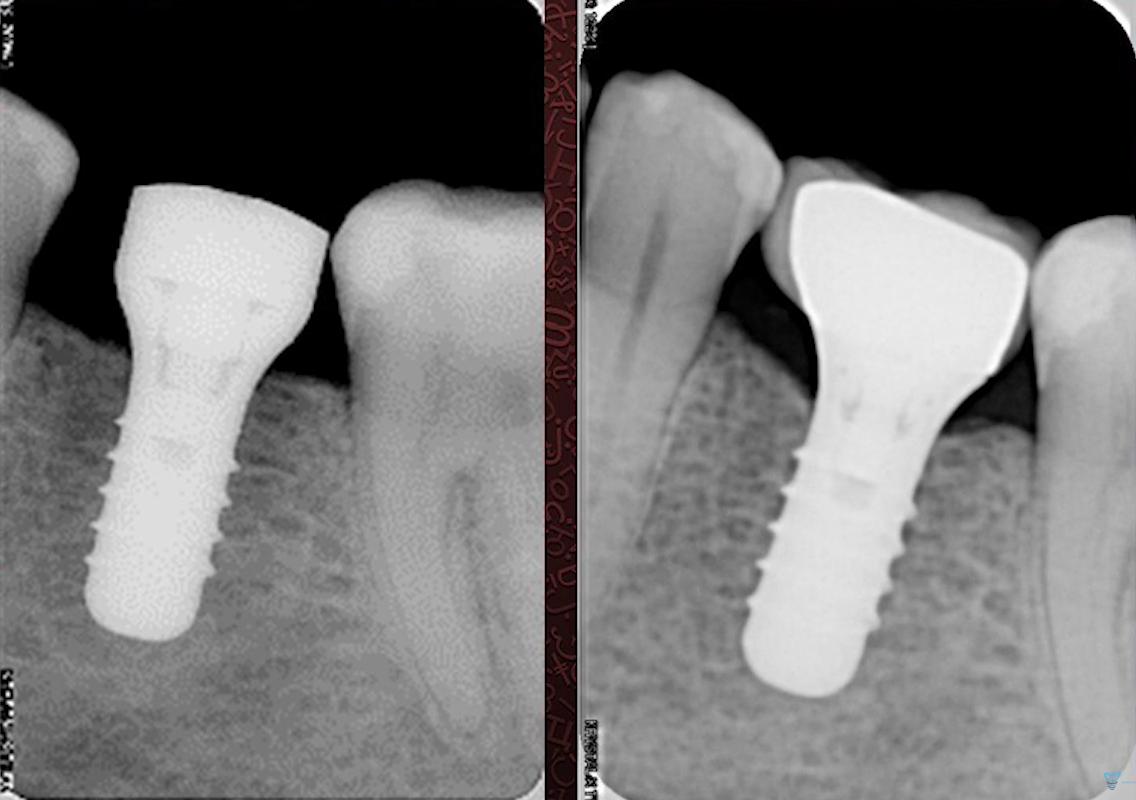

But if you compare three x-rays:

- Immediately after implantation

- In 3 months

- After 12 months…you can see changes in the level of the marginal bone.

…you can see changes in the level of the marginal bone.

X-rays: immediately after implantation, 3 months and 12 months after implantation. YouTube/ Implantarium/ Rauf Aliyev

In summary, this “pure experiment” case demonstrates that the initial gingival thickness is the decisive factor for bone remodeling. Despite other positive factors such as:

- Broad alveolar ridge

- Good volume of keratinized attached gingiva

- Double platform switchingThe outlook for this restoration is still good, the formation of the gingival junction is complete, and the remaining bone contact is sufficient for implant stability, as the risk of gingival recession is minimal. However, if the patient has other negative factors, a loss of 1-2 mm of marginal bone can be critical for implant survival.